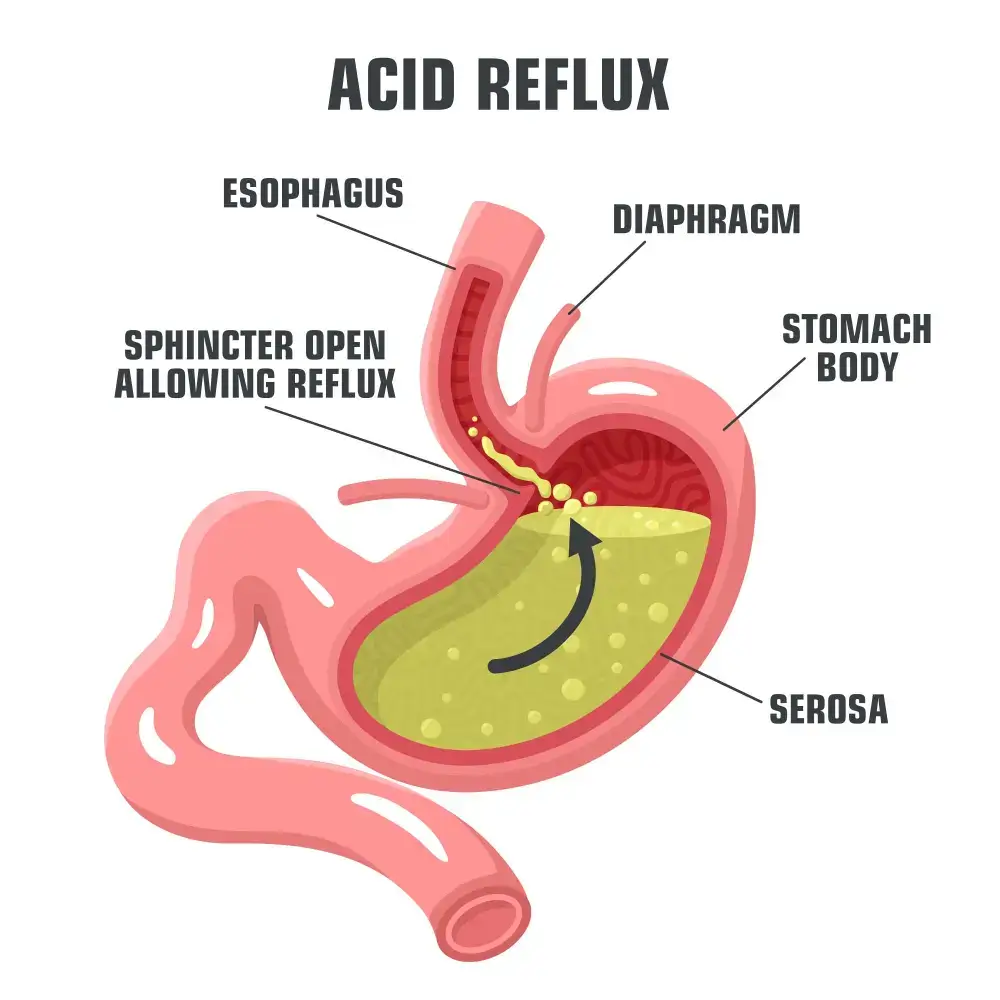

- Acid Reflux • Georgetown • Acupuncture • Natural Health Clinic of Halton (March 5, 2022)